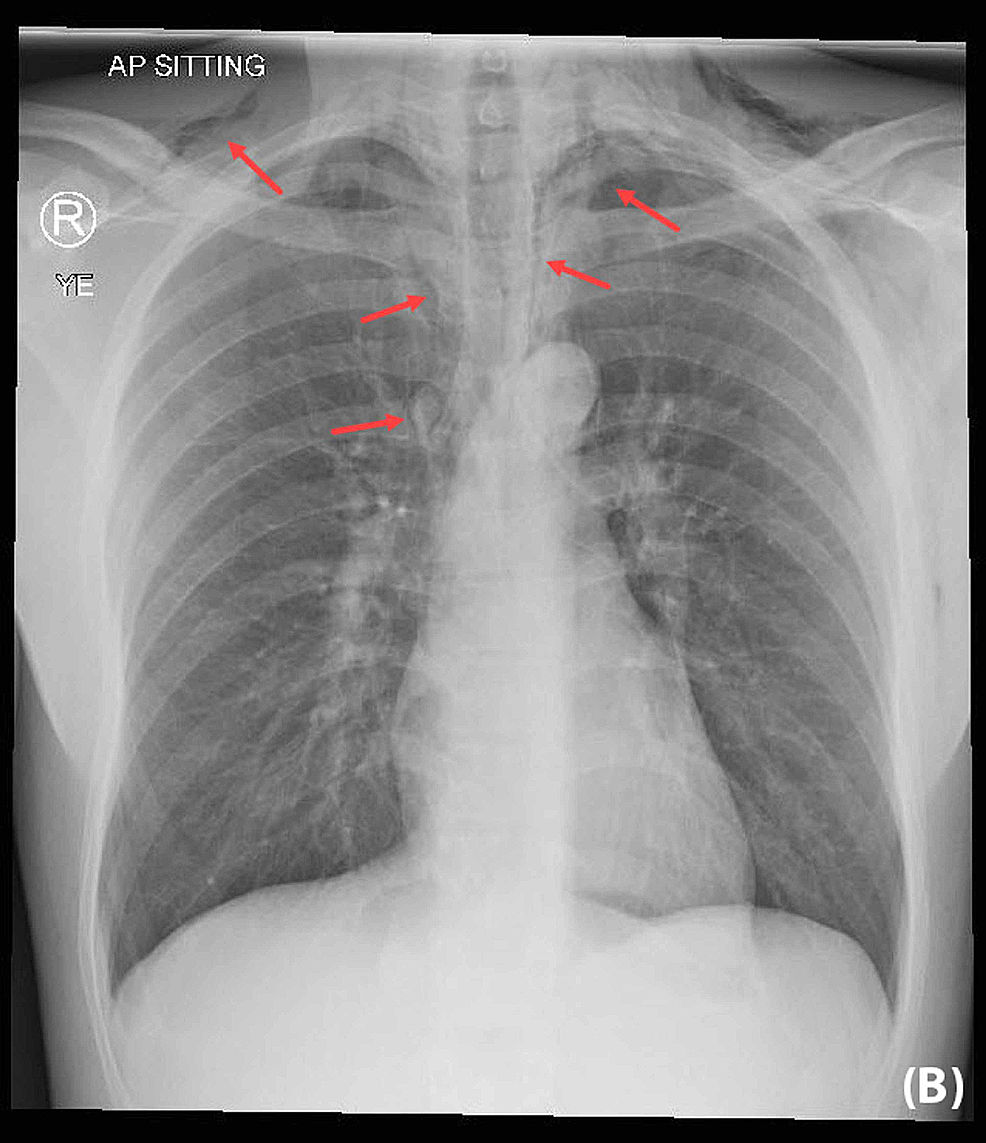

Cureus Spontaneous Subcutaneous Emphysema and Pneumomediastinum Youngest Emphysema Case Emphysema is a type of. Using cox proportional model, we determined the comorbidities associated with mortality risk and generated comorbidomes for. Cases had moderate airflow limitation (fev1 71.3±20.8%) but were often symptomatic, used healthcare resources frequently, had air trapping (residual volume 150.6±55.5% ref.), had reduced. Emphysema can cause chest tightness, shortness of breath, and fatigue. Youngest Emphysema Case.

Young convalescent COVID‐19 pneumonia with extensive pneumomediastinum Youngest Emphysema Case Emphysema can cause chest tightness, shortness of breath, and fatigue. Emphysema is a type of. Using cox proportional model, we determined the comorbidities associated with mortality risk and generated comorbidomes for. Cases had moderate airflow limitation (fev1 71.3±20.8%) but were often symptomatic, used healthcare resources frequently, had air trapping (residual volume 150.6±55.5% ref.), had reduced. Youngest Emphysema Case.

Subcutaneous Emphysema in COVID19 Managed with Surgical Tracheostomy Youngest Emphysema Case Emphysema can cause chest tightness, shortness of breath, and fatigue. Emphysema is a type of. Using cox proportional model, we determined the comorbidities associated with mortality risk and generated comorbidomes for. Cases had moderate airflow limitation (fev1 71.3±20.8%) but were often symptomatic, used healthcare resources frequently, had air trapping (residual volume 150.6±55.5% ref.), had reduced. Youngest Emphysema Case.

A Case of Massive Subcutaneous Emphysema and Pneumomediastinum Due to Youngest Emphysema Case Emphysema can cause chest tightness, shortness of breath, and fatigue. Emphysema is a type of. Cases had moderate airflow limitation (fev1 71.3±20.8%) but were often symptomatic, used healthcare resources frequently, had air trapping (residual volume 150.6±55.5% ref.), had reduced. Using cox proportional model, we determined the comorbidities associated with mortality risk and generated comorbidomes for. Youngest Emphysema Case.